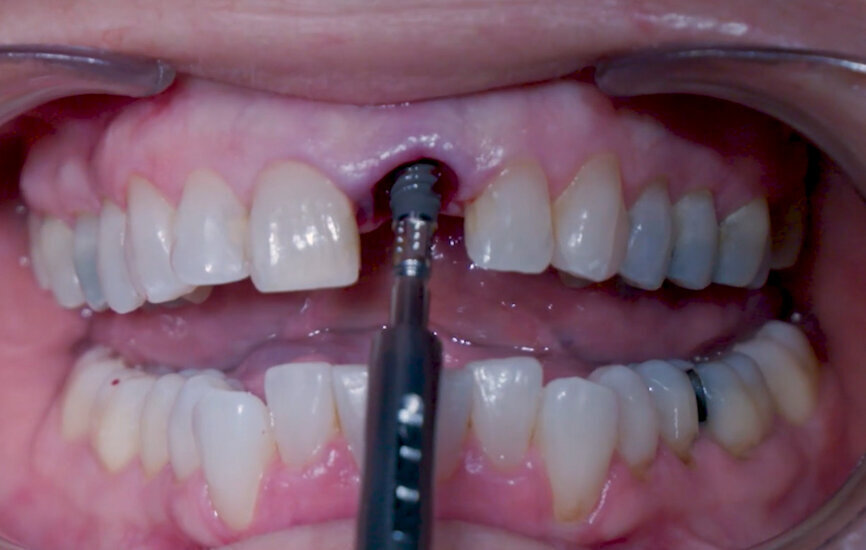

Fig. 14: Straumann XenoFlex being applied in labial gap.

Fig. 15: Straumann XenoFlex being applied in labial gap.

Intra-sulcular incisions were performed to release the marginal gingival fibres to allow a minimally invasive extraction. The socket was carefully cleaned to remove any ligament and debris left. Special attention was given to assessing the alveolar wall integrity. A distance of 3 mm was observed between the gingival margin and the labial wall margin. Implant bed preparation considered a medium-density bone workflow, starting with the needle drill aimed at the palatal wall to create an entry point for the next drills, creating an osteotomy that allows for a greater area of implant engagement (Fig. 5). The Ø 2.2 mm pilot drill was used to the respective implant length planned, followed by the use of an alignment pin to check the 3D orientation (Figs. 6 & 7). The Ø 2.8 mm and Ø 3.2 mm drills were used to finalise the osteotomy (Fig. 8). The site was then properly probed to assess for possible wall perforation. A 4 × 14 mm implant was placed, starting with the surgical handle engaging the apical part of the implant, following the same orientation as that of the needle drill and correcting the implant direction as it moved within the osteotomy (Figs. 9 & 10). Primary stability (45 Ncm) was achieved at the final position. After placement, the implant position was verified horizontally with an occlusal mirror and vertically with a surgical probe, and at this point, the abutment gingival height was selected (Figs. 11 & 12). A healing abutment was placed on to the implant (Fig. 13) to protect the connection so that granular bone substitute (Straumann XenoFlex) could be applied in the gap between the implant and labial wall. This was gently compacted in with the 2.8 mm side of the surgical probe (Figs. 14–16). Collacone (botiss biomaterials) was used to keep the bone granules away from the gingival margins in order to avoid softtissue fenestration and fibroblastic infiltration (Figs. 17 & 18).